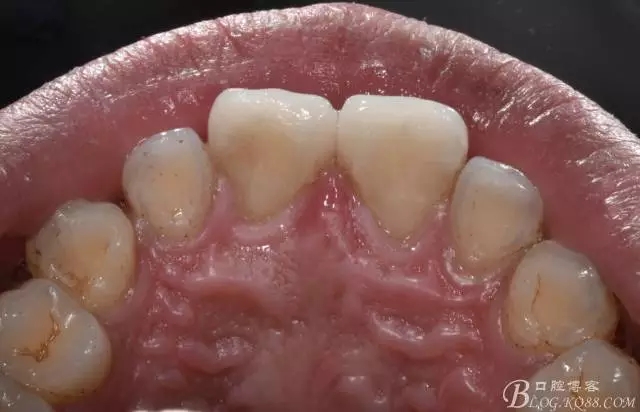

舌側(cè)照